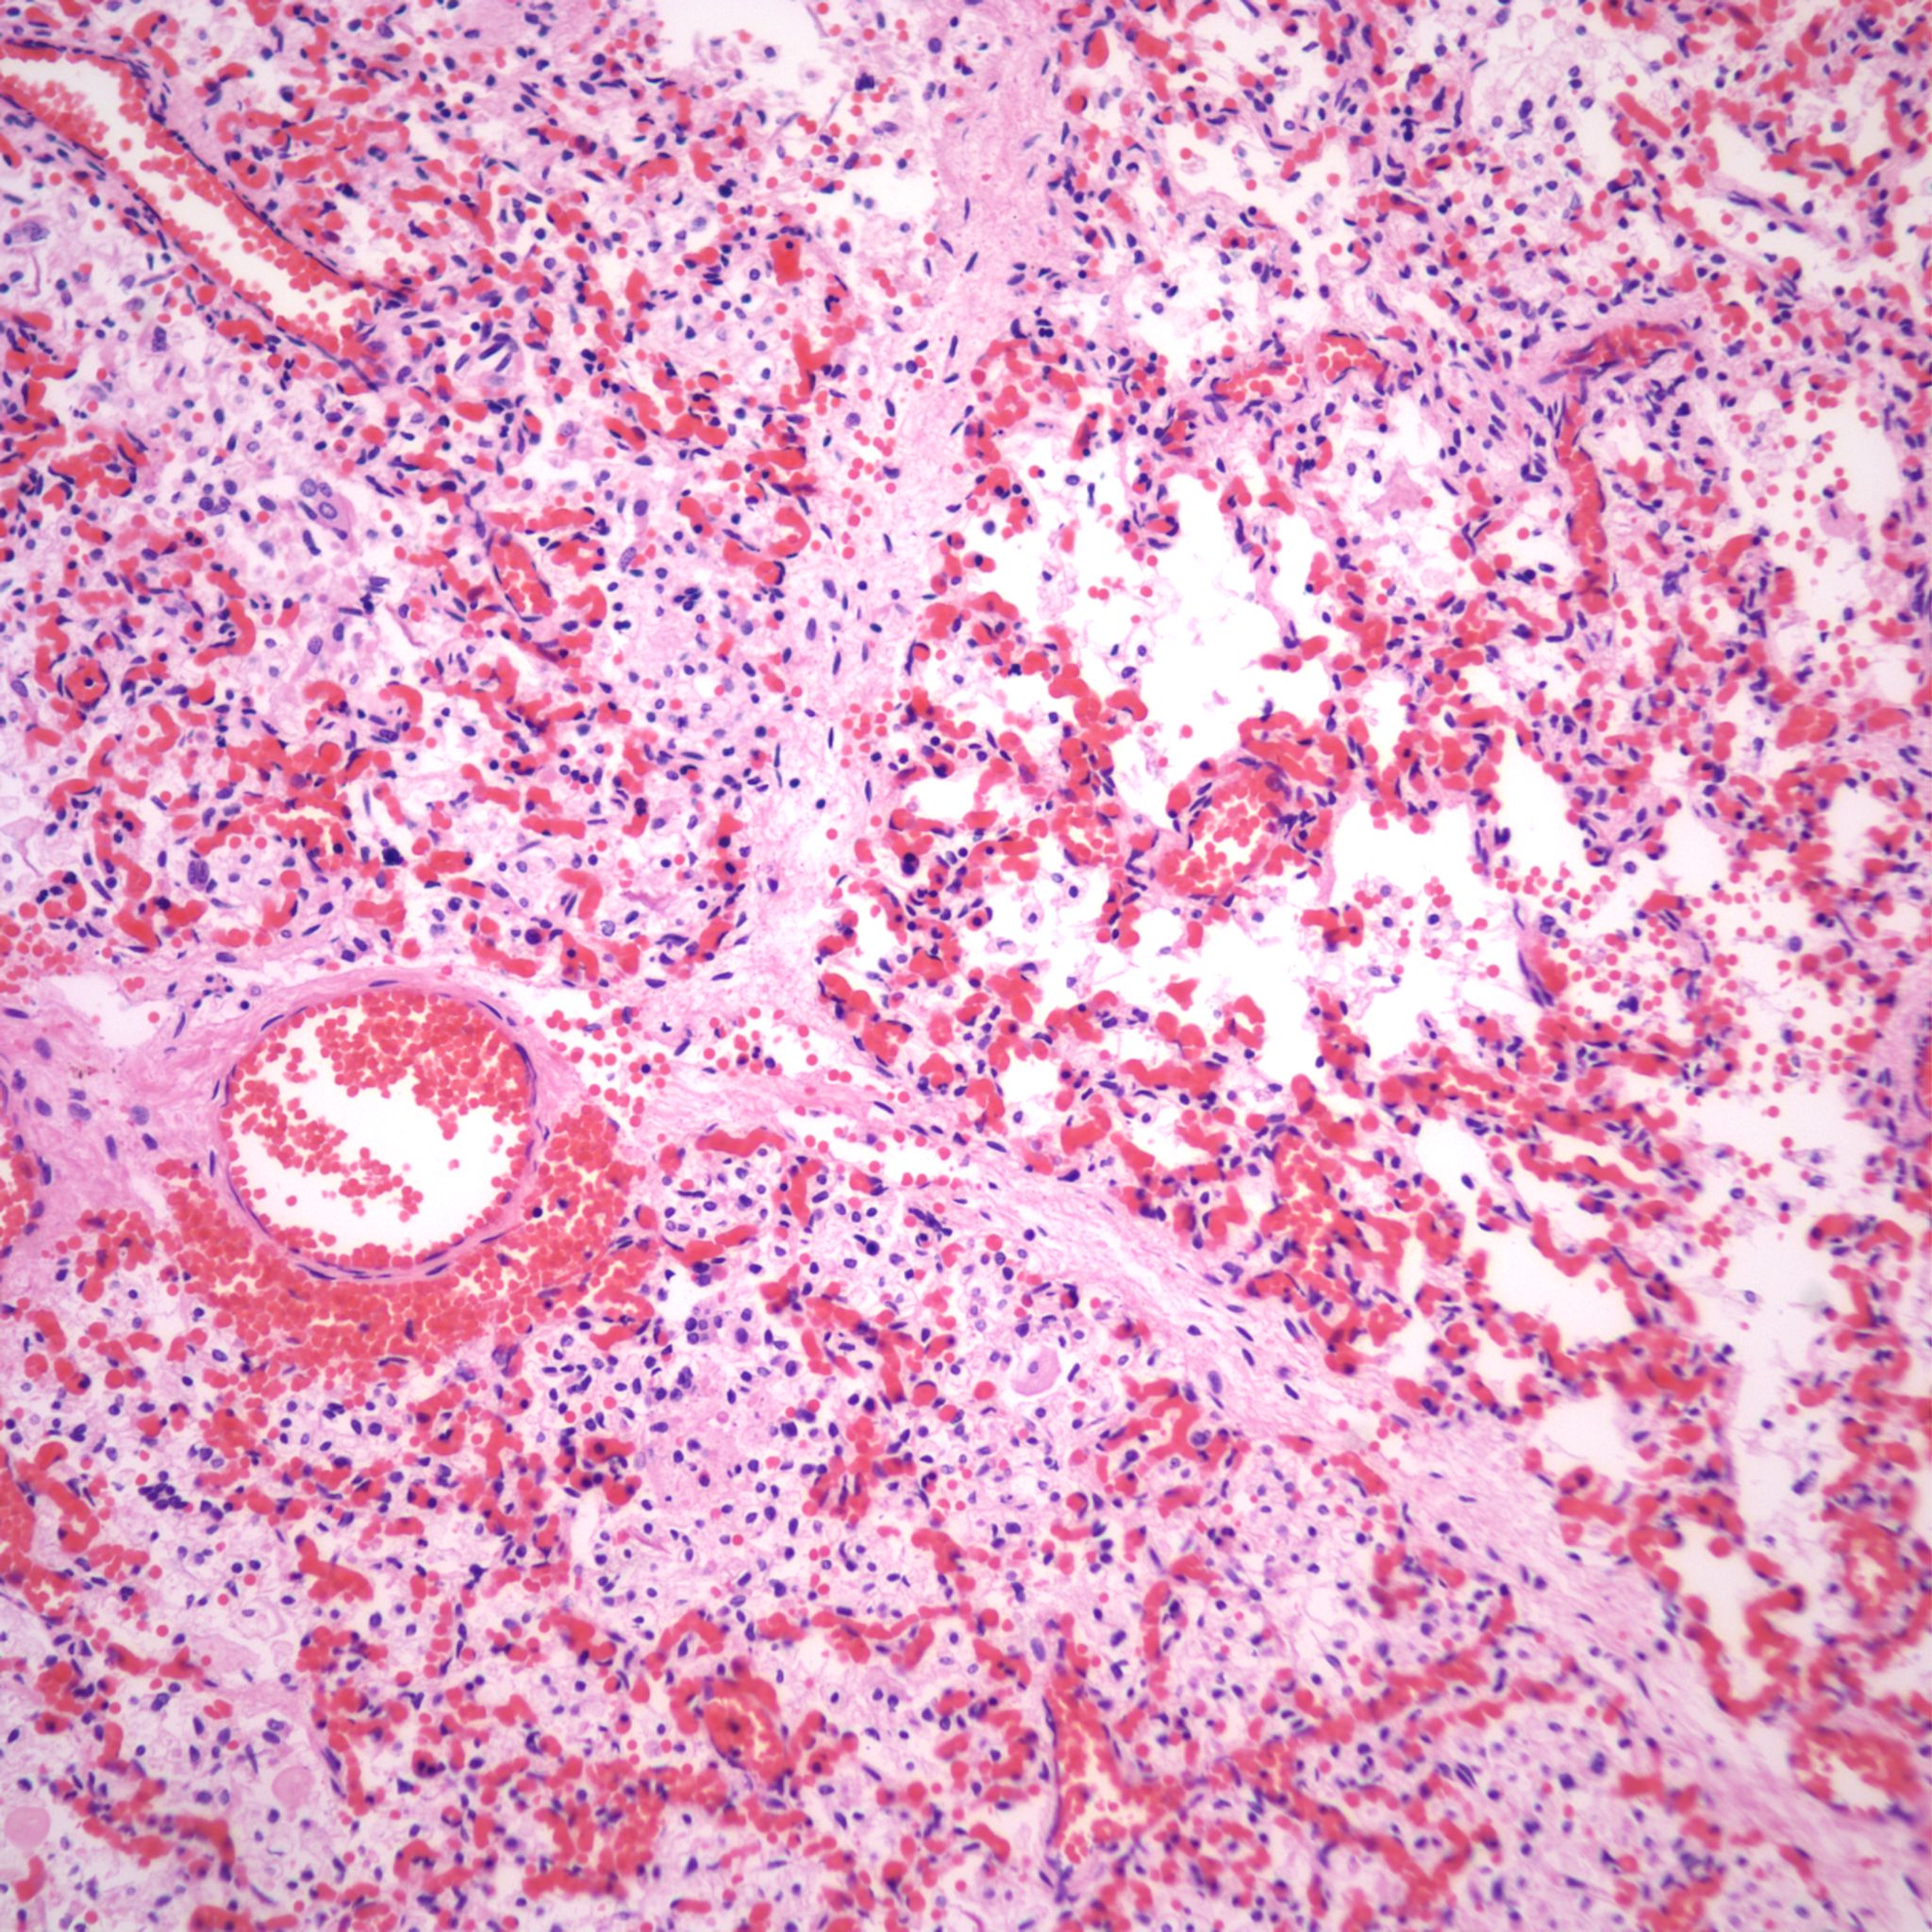

Beside hemorrhage in the visceral pleura, there may be deeper connective tissue interstitial hemorrhage in the lung. The capillaries in other areas of the lung with pleural petechiae are often engorged as well, and the rigors of gasping and pressure change may account for deeper hemorrhages (Fig 20a, b).

Focal hemorrhages may also be found in the airways usually with evidence of hemorrhages in other organs suggestive of disseminated intravascular coagulation and shock (Fig 21).

The mechanism for many hemorrhages is obscure. With elevated left atrial pressure, for example with heart failure, but more acutely with closure of the ductus arteriosus, elevated atrial pressure would be reflected in dilatation of the pulmonary veins in the septa (Fig 22).

In turn this pressure should passively increase pulmonary capillary pressure. A similar increase in atrial pressure occurs with sudden acute twin transfusion prior to death (Fig 23).